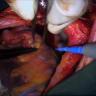

This video demonstrates a clinical case report and accompanying intraoperative footage of a laparoscopic transgastric resection of surgical mesh that was previously placed for hiatal hernia repair... More